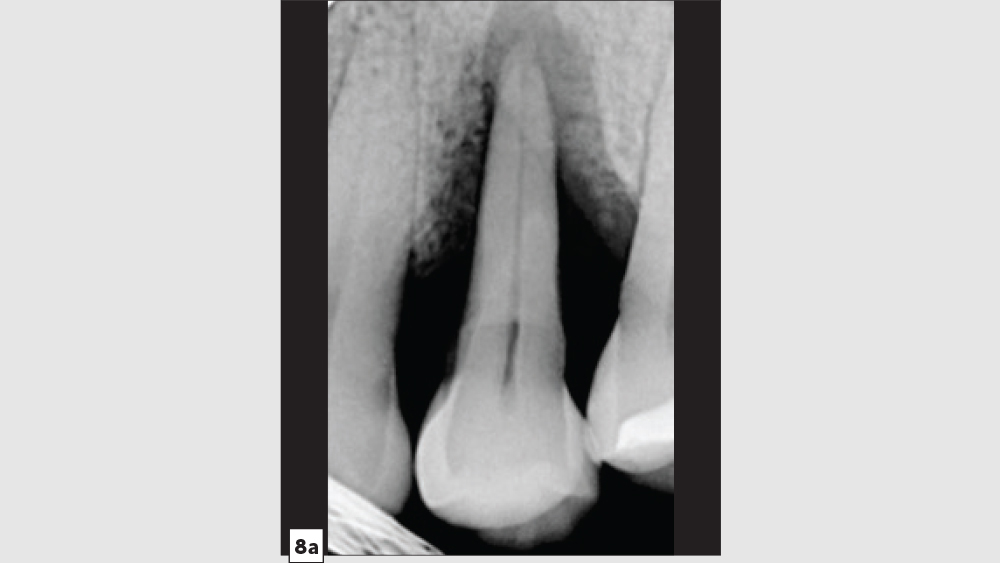

Three-Walled Socket Bone Grafting Technique (Figs. 8a–8d)

Figure 8a

Figures 8a–8d: Three-walled socket: failing tooth with bone loss (8a), example of three-walled socket (buccal and lingual walls missing) (8b), graft with tent screw (8c), post-op healing (8d).